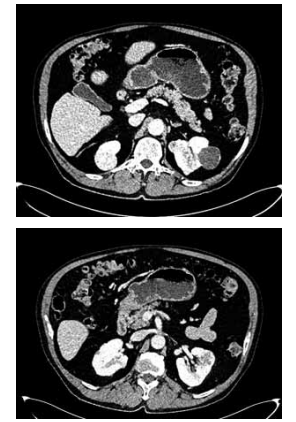

Observe a imagem da tomografia a seguir:

(Arquivo pessoal; imagem usada com autorização)

Qual diagnóstico deve ser considerado com base nos achados da tomografia e qual diagnóstico concomitante está associado à sua hipótese?